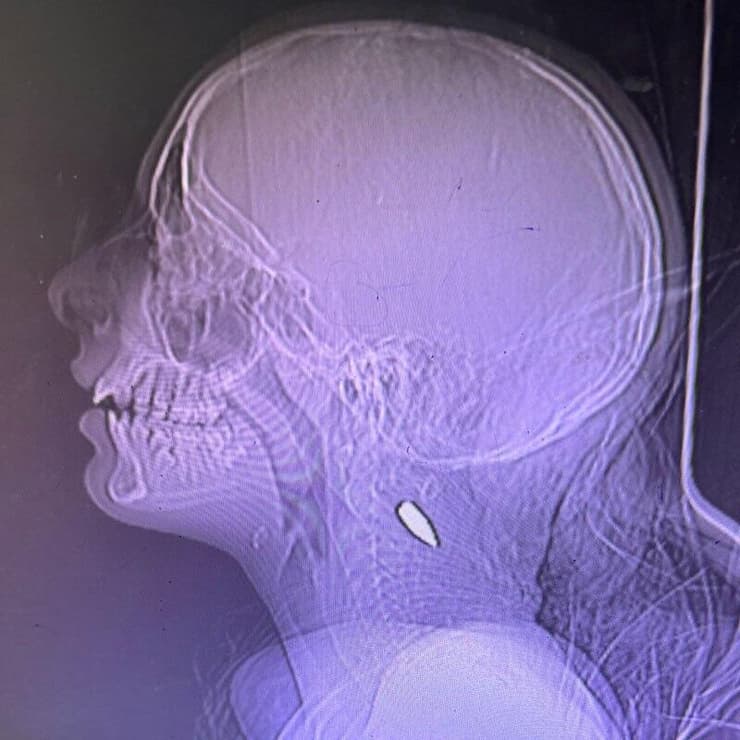

במאמר נכללו צילומי רנטגן שהתקבלו מרופאה שעבדה בחאן יונס, בהם מוצגים כדורים שחדרו לראשי גופות, אשר נטען שהן של ילדים. עם זאת, כמה גורמים ערערו על אמינות הצילומים ועל ההאשמות הנלוות אליהם. קצין משטרה בארצות הברית ניתח את המאפיינים הבליסטיים של כלי הנשק המדובר וטען כי בהתבסס על מהירות הקליע, הכדור היה חייב לחדור לחלוטין את גולגולת הילד, ולא להישאר בגוף כפי שהוצג בצילומים. בנוסף, הוא הביע ספק בנוגע לתקופת שהותה של הרופאה בחאן יונס, בשל פעילות צה"ל האינטנסיבית באזור באותה תקופה.

רדיולוגים נוספים הביעו ספקות לגבי הממצאים שלדבריהם לא הראו סימנים שמאפיינים פגיעות מירי במהירות גבוהה, כמו שברים בעצמות או קרעים ברקמות, מה שמעורר שאלות בנוגע לתקפות הטענות. מומחים לבליסטיקה טענו גם הם כי הפגיעות המוצגות בצילומים לא תואמות פגיעות שנגרמות מכלי נשק בהם צה"ל משתמש. לדברי המומחים, כדורי 5.56 מ"מ שנורים מכלי נשק כמו M-16 או תבור גורמים לנזקים חמורים יותר, שכוללים יצירת פצע יציאה רחב - דבר שלא מופיע בצילומים שהוצגו במאמר.